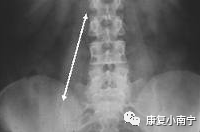

曾经有腰部不适的患者到医院检查后,竟然发现是髂腰肌脓肿(abcess)所造成的!所以我们在看腰椎前后照的X光时也要注意到psoas muscle line的大小:若是看不清楚这条线就要怀疑腹腔中的器官有严重伤害,尤其有外伤病史的患者。若是这条线过于肿大,那可能还要追踪MRI是否有发现脓肿或肿瘤的现象,特别是胸腰椎结核菌感染的患者。

图片